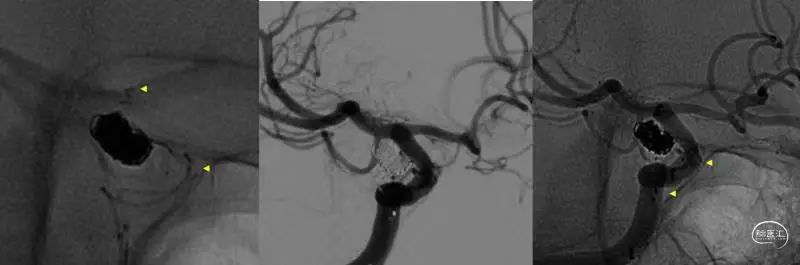

复查随访

8个月复查时显示动脉瘤瘤颈处复发。

图4

二次手术过程

使用Jailing技术支架辅助栓塞,应用Atlas 4.5-21(图5:黄色三角提示术中及术后支架两端的mark位置)

图5

栓塞完毕后回撤支架导丝时支架移位。